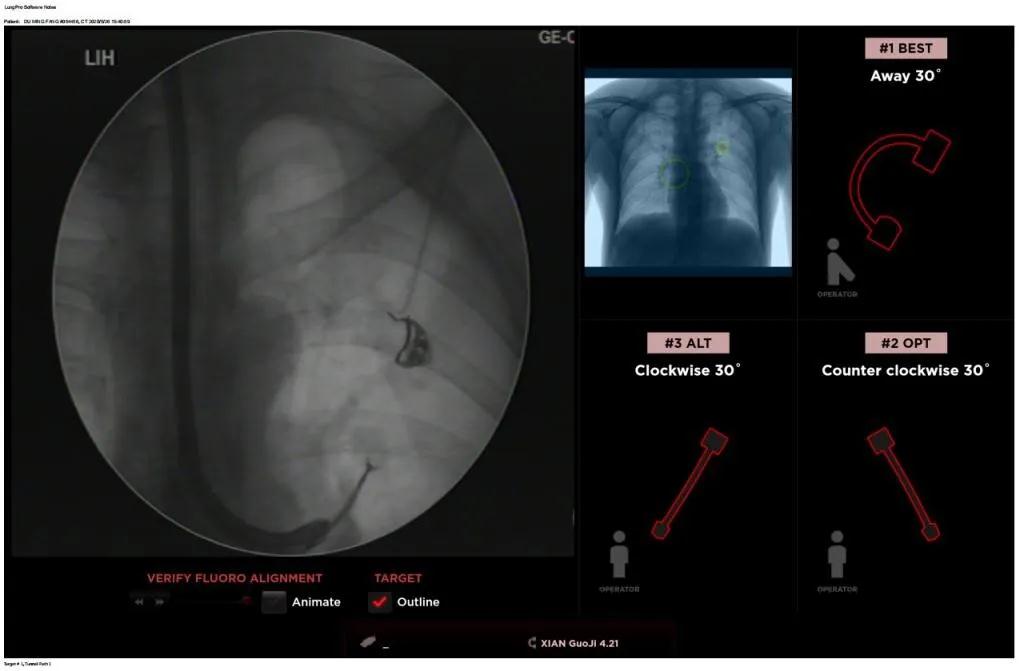

西安國際醫(yī)學(xué)中心醫(yī)院呼吸內(nèi)科完成西北地區(qū)首例LungPro全肺導(dǎo)航系統(tǒng)引導(dǎo)下BTPNA手術(shù)

近日,西安國際醫(yī)學(xué)中心醫(yī)院胸科醫(yī)院歐陽海峰副院長完成西北地區(qū)首例LungPro全肺導(dǎo)航系統(tǒng)引導(dǎo)下經(jīng)支氣管鏡跨肺實(shí)質(zhì)肺外周結(jié)節(jié)活檢術(shù)。

患者是一位59歲的男性,入院診斷左固有上葉前段肺小結(jié)節(jié),大小1.5cm*1.5cm。因?yàn)椴≡钆c支氣管不相通,無法開展經(jīng)支氣管自然腔道的活檢,而且病變距離胸壁較遠(yuǎn)、肋骨阻隔進(jìn)針線路、病灶周圍有血管包繞,如果進(jìn)行CT引導(dǎo)下經(jīng)皮肺穿刺活檢,則存在較大的氣胸、出血等并發(fā)癥的風(fēng)險(xiǎn)。

經(jīng)過充分的討論后,歐陽海峰副院長決定為患者實(shí)施LungPro全肺導(dǎo)航系統(tǒng)引導(dǎo)的經(jīng)支氣管跨肺實(shí)質(zhì)肺外周結(jié)節(jié)活檢術(shù)。Broncus導(dǎo)航系統(tǒng)LungPro具有全球領(lǐng)先獨(dú)創(chuàng)的BTPNA技術(shù)(支氣管鏡下跨結(jié)節(jié)抵達(dá)術(shù)),可以實(shí)現(xiàn)對(duì)氣道外周孤立性肺小結(jié)節(jié)的精準(zhǔn)定位,建立直接通往氣道外病變部位的通道,以實(shí)現(xiàn)全肺的診斷及后續(xù)治療。這項(xiàng)技術(shù)不僅彌補(bǔ)了現(xiàn)有支氣管鏡技術(shù)由于受限于病變部位是否有氣道可通向以及無法準(zhǔn)確定位病變部位而造成的較低診斷率,同時(shí)還彌補(bǔ)了CT引導(dǎo)下經(jīng)胸穿刺(TTNA)無法適用于某些特定部位如中央及肩胛骨等結(jié)節(jié)的問題,并且還避免了經(jīng)胸穿刺給患者帶來氣胸、出血的高風(fēng)險(xiǎn),可有效提高肺部結(jié)節(jié)及早期肺癌診斷陽性率,亦可用于早期肺癌的射頻消融或微波治療,具有微創(chuàng)、安全、同期雙肺診療等優(yōu)勢。

BTPNA技術(shù)整合了虛擬導(dǎo)航支氣管鏡VBN、氣道內(nèi)超聲r(shí)EBUS、TBNA、高壓球囊擴(kuò)張、X線輔助等多項(xiàng)三、四級(jí)呼吸內(nèi)鏡技術(shù)。歐陽海峰副院長有3000 TBNA、1000 rEBUS、500 VBN、800 球囊擴(kuò)張方面的技術(shù)積累,10年來個(gè)人每年完成三、四級(jí)呼吸內(nèi)鏡手術(shù)1200余例,這有效保障了BTPNA技術(shù)的順利開展。

團(tuán)隊(duì)術(shù)前進(jìn)行了精心的準(zhǔn)備,通過高分辨率CT建立了導(dǎo)航路徑,在麻醉科手術(shù)室的配合下,借助LungPro引導(dǎo)順利的確定了病灶部位、建立隧道并實(shí)施活檢,術(shù)后患者恢復(fù)順利出院。